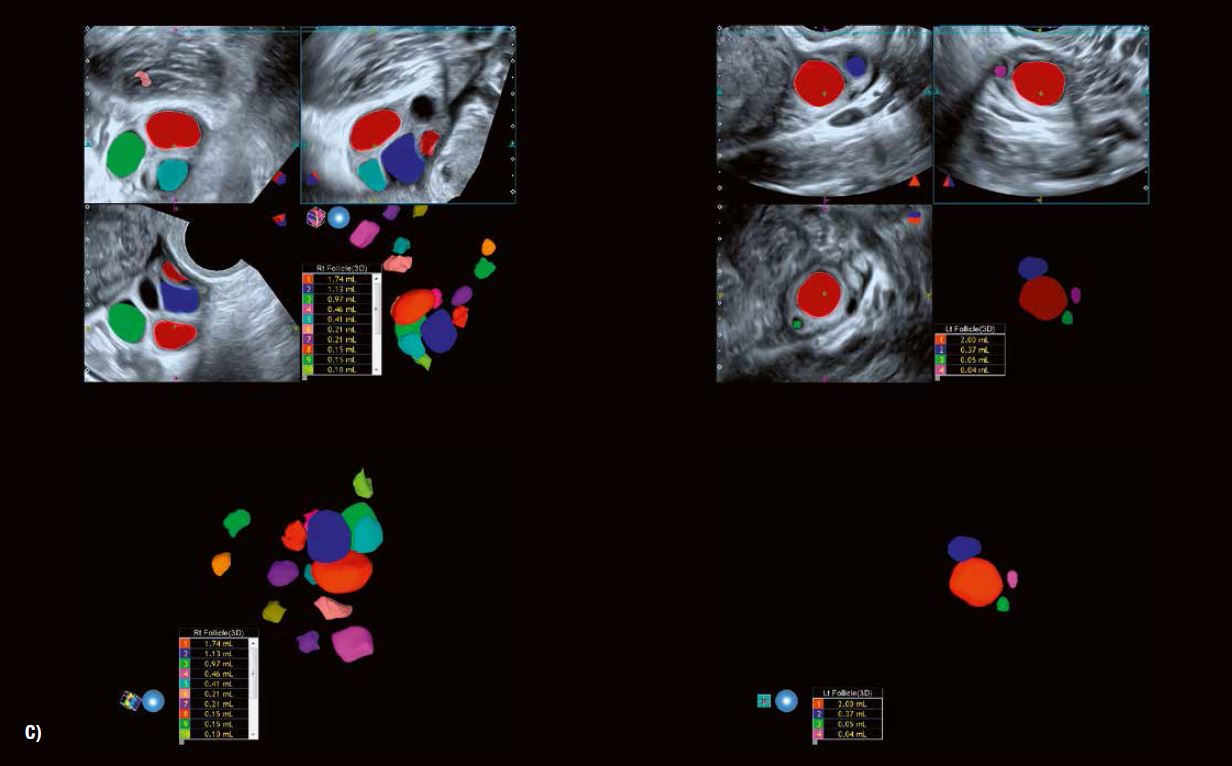

«Кістозний» вигляд дозволяє візуалізувати антральні фолікули розміром від 2 до 3 мм. Розмір антральних фолікулів коливається від 2 до 8 мм. Підрахунок антральних фолікулів, що проводиться перед процедурами ЕКЗ або для оцінки фолікулярного запасу яєчників у пацієнток в періоді менопаузи, точно вимірюється за допомогою 3D УЗД вагінальним датчиком проводиться приблизно на 3–5 день циклу після початку менструації.

Ультразвукове дослідження та моніторинг росту фолікулів під час природного або пов'язаного з допоміжними репродуктивними технологіями циклу вже давно стали загальноприйнятою практикою. Прогрес у технології УЗД значно підвищив можливості оцінки дозрівання фолікулів та прогнозування початку овуляції (рис. 5). Сканування у високій роздільній здатності в сірій шкалі демонструє потовщення стінки фолікула внаслідок розвитку гранульозних та текальних клітин. Внутрішнє відшарування гранульозних клітин можна виявити в овуляційному фолікулі. 3D-візуалізація Fly Thru часто дозволяє розпізнати кумулюсну масу безпосередньо перед овуляцією (рис. 6). Розмір фолікула на початку овуляції може варіюватися від 1,8 до 3,0 см. Примітка: розмір фолікула сам по собі не завжди є показником його дозрівання.

SMI показує збільшення периферичної васкуляризації, пов'язаної з дозріванням фолікулів (Граафа). Він також дозволяє точно виміряти час овуляції в рамках циклу, що контролюється. Було доведено, що підвищена васкуляризація пов'язана  з овуляційним статусом і розвитком сприятливого ендометрію в періоді овуляції (рис. 5 + 6). Дослідження показали хорошу кореляцію між периферичним ангіогенезом фолікула в періоді овуляції та після овуляції з рівнями естрогену та прогестерону в сироватці крові відповідно. SMI забезпечує  надійний засіб оцінки функції лютеїнової фази як частини моніторингу фертильності та оцінки дуже  ранньої вагітності (рис. 9+13).

Рис. 5 B: 3D-візуалізація поверхні чітко окреслює фолікули на обох яєчниках.

Рис. 5 C: Автоматичне вимірювання об'єму фолікулів із функцією кольорового кодування має очевидну перевагу з точки зору моніторингу циклів допоміжних репродуктивних технологій що забезпечує дуже ефективну оцінку кількості фолікулів, а також їх зростання.